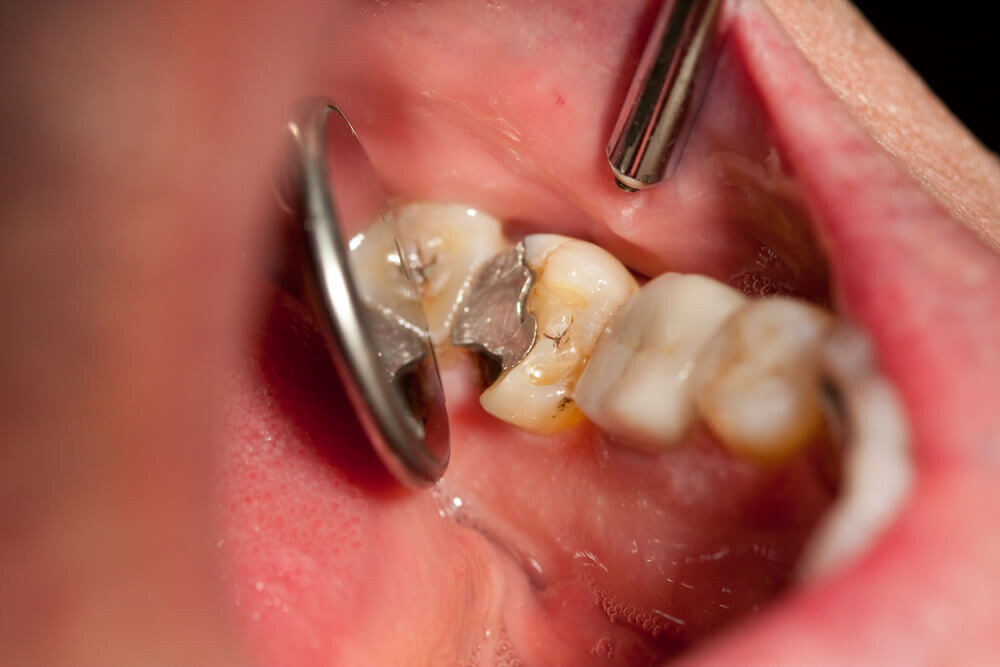

A damaged filling

A damaged filling can cause toothache when the filling is no longer able to protect your tooth from external stimuli. When a filling is damaged, it can create an opening in the tooth, allowing bacteria to penetrate and cause an infection, leading to inflammation, swelling, and pain. Additionally, if you don’t replace the filling in time, it may cause your tooth to weaken or crack. A damaged filling may also cause sensitivity to hot and cold food and drinks.